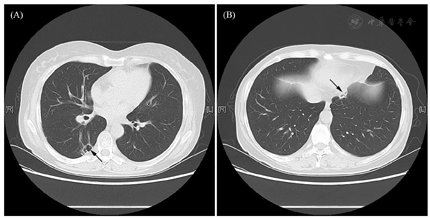

影像学资料:鞍区MRI平扫+增强提示垂体后叶及垂体柄信号异常(图1)。甲状腺超声:甲状腺实质弥漫性病变,不除外桥本甲状腺炎。全身浅表淋巴结超声波检查提示双侧锁骨上区多发稍大淋巴结,右侧大者1.0 cm×0.7 cm,左侧大者0.9 cm×0.7 cm。肺CT:右肺下叶背段空洞合并双肺多发性结节影(图2)——化脓性感染、肺脓肿?经CT引导下右肺下叶结节穿刺活检,病理学检查结果回报:肺间隔明显增宽,部分实变,伴大量淋巴细胞、浆细胞及少许嗜酸性粒细胞浸润(图3)。免疫组化染色提示CD138+、IgG4+,部分热点区域IgG4+细胞约为40个/高倍视野。特殊染色:弹力纤维+,革兰氏-,PSA-,PASM-,黏液卡红-。请结合临床除外IgG4相关性疾病(IgG4-related disease, IgG4-RD)。未见明确真菌、结核及肿瘤性病变。腹部CT未见异常。

治疗上,确诊为IgG4-RD后,予强的松龙40 mg QD口服治疗。针对尿崩症,给予醋酸去氨加压素:早0.1 mg、午0.05 mg、晚0.1 mg,治疗后每日入量约2 000~3 000 ml,尿量2 000~3 000 ml,出入量大致平衡,血钠降至正常。对于糖尿病,予阿卡波糖控制血糖,空腹血糖约5~7 mmol/L,餐后2 h血糖约7~10 mmol/L。对于类风湿性关节炎,给予来氟米特、硫酸羟氯喹治疗。1个月后患者病情稳定出院。出院前复查空腹C肽561.5 pmol/L。甲状腺功能:TT3 0.93 ng/ml、TT4 8.1 μg/dl、FT3 2.28 pg/ml、FT4 0.87 ng/dl、TSH 1.44 mIU/L。皮质醇:08∶00 17.5 μg/dl。ACTH:08∶00 18.3 pg/ml。出院后患者定期随诊,门诊复查HbA1C 6%。出院半年后强的松龙改为强的松。目前醋酸去氨加压素为早0.2 mg、午0.1 mg、晚0.1 mg,强的松5 mg qd,IgG4下降至0.534 g/L,患者病情稳定,复查肺部病变较前缩小(图4)。